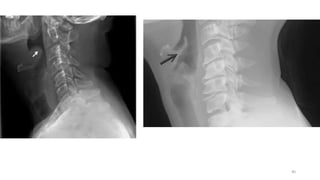

Radiographic features of epiglottitis include:

• An enlarged epiglottis protruding from the anterior wall of the

hypopharynx (the "thumb sign“)

• Loss of the vallecular air space

• Thickened aryepiglottic folds

• Distended hypopharynx (nonspecific).

• Straightening or reversal of the normal cervical lordosis

ACUTE EPIGLOTTITIS CONT…